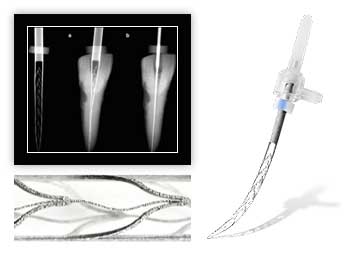

Имплантация зубов

- Имплантация нижних зубов

- Одномоментная имплантация зубов

- Имплантация верхних зубов

- Полная имплантация зубов

- Синус лифтинг

- Имплантация зубов под ключ

- Имплантация одного зуба

- Имплантация передних зубов

- All on 6

- All on 4

- Импланты Ankylos

- Импланты Osstem

- Импланты Straumann

- Имплантация жевательных зубов

- Имплантация зубов под наркозом

Имплантация зубов

-

Внутрикостная дентальная имплантация с применением имплантатов, проведение операции (без учета импланта)

34129

Импланты Ankylos

-

Дентальная имплантация с применением имплантатов Ankylos (стоимость без учета снимка и анестезии)

89937

Импланты Osstem

-

Дентальная имплантация с применением имплантатов Osstem (стоимость без учета снимка и анестезии)

71382

Импланты Straumann

-

Дентальная имплантация с применением имплантатов Straumann (стоимость без учета снимка и анестезии)

102415